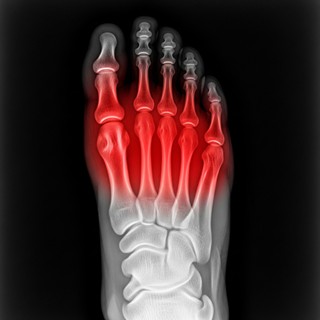

אם אתם חווים כאב חד, תחושת שריפה או הרגשה שאתם דורכים על "גולה" באזור הקדמי של כף הרגל (הכריות) – סביר להניח שאתם סובלים ממטטרסלגיה (Metatarsalgia). זהו מצב שבו מופעל לחץ עצום ובלתי פרופורציונלי על ראשי עצמות המסרק, מה שמוביל לדלקת, שחיקה וכאב יומיומי שמקשה מאוד על ההליכה והעמידה.

הטכנולוגיה – לראות את נקודת הלחץ המדויקת במטטרסלגיה, מילימטר אחד של חוסר דיוק במיקום הכרית המרופדת יעשה את ההבדל בין הקלה משמעותית לכאב מציק. לכן, אנו מבצעים בדיקת הליכה ממוחשבת (Gait Analysis) וסריקה תלת-ממדית (3D). הטכנולוגיה מציגה לנו "מפת לחצים" מדויקת בזמן תנועה (במיוחד בשלב הדחיפה של הרגל קדימה), ומאפשרת לנו למקם את התמיכה בנקודה המושלמת עבורכם.